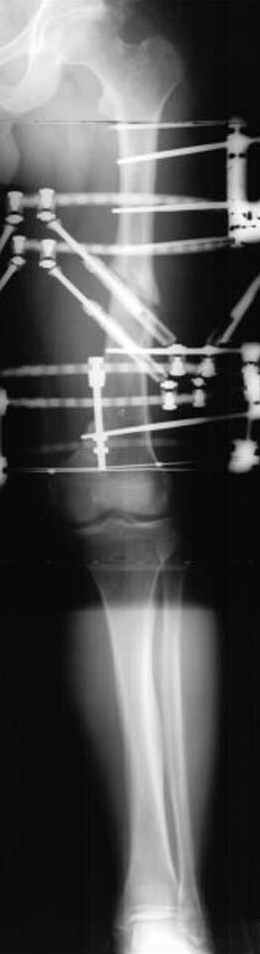

Отправитель: Djoldas Kuldjanov 23 Ноябрь 2004, 18:21

пластическая модель; и коррекция бедра аппаратом Илизарова.

Имею другие снимки тоже, получится как отчет о моей работе.